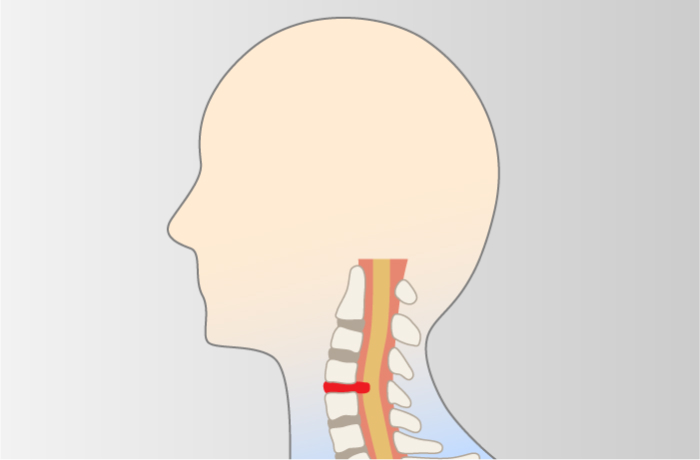

頸椎ヘルニア

-

椎骨間にある髄核が飛び出し、脊髄や神経根を圧迫して痛みなどが生じる

頸部神経根症

頸部神経根症

-

首の骨に負荷が継続的にかかり続けることで椎間板が変性し、骨棘を形成することよって、頚椎にある「椎間孔」が狭くなり、神経根が圧迫された刺激されて肩や腕の痛みや痺れといった症状をきたす。